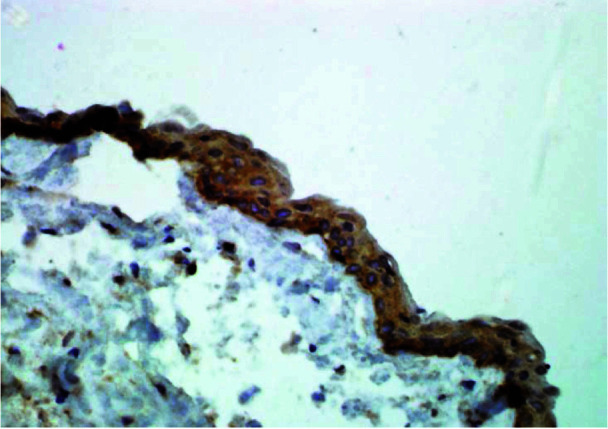

Results: The PXN marker was detected in the cytoplasm of tumor cells (unicystic and solid ameloblastoma) and the epithelial layer of cysts (DC and OKC). The intensively stained marker of PXN was observed in 9 cases (64.3%) of the DC, 14 cases (70%) of OKC, 12 cases (75%) of unicystic ameloblastoma, and 13 cases (72.2%) of solid ameloblastoma. However, there was not statistical difference of PXN protein expression between DC and OKC (p Value = 0.51) and unicystic and solid ameloblastoma (p = 0.58), also the same was true for cysts and tumors (p = 0.37).